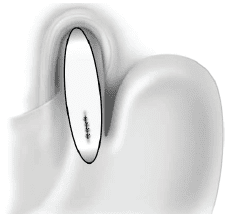

La reparación de la mucosa requiere sutura con puntos separados con una aguja fina y sutura absorbible 5-0 (figura 2). La fundoplicatura debe cubrir la sutura sin tensión y se deja un drenaje activo blando (Jackson- Pratt) proximal a la fundoplicatura (no en contacto con la sutura) (figura 3) 6.

Reparación de la mucosaFigura 2. Reparación de la mucosa con puntos separados con aguja fina y sutura absorbible 5-0

Fundoplicatura parcial anterior y drenaje activo blandoFigura 3. Fundoplicatura parcial anterior (fundoplicatura de Dor) y drenaje activo blando